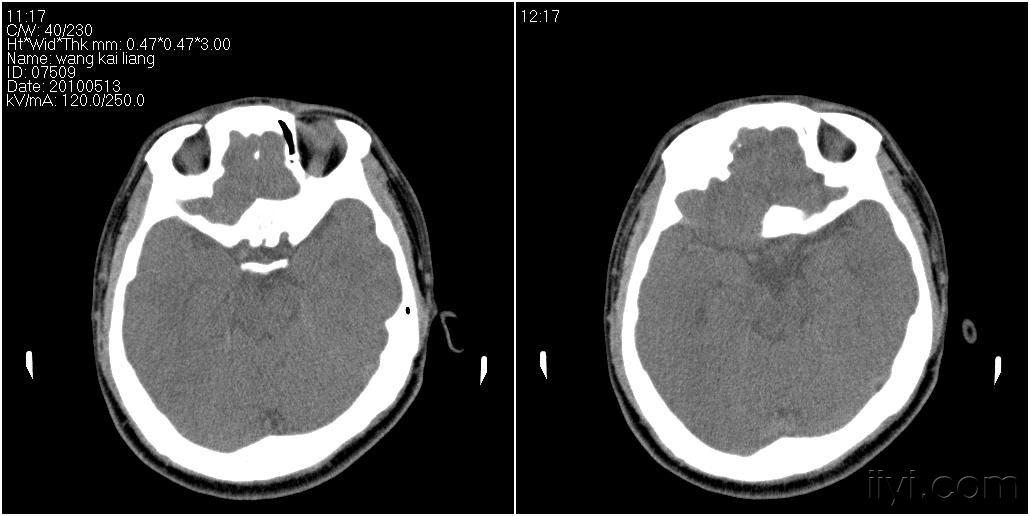

男性27岁患者要求头颅扫描发现蝶窦病变